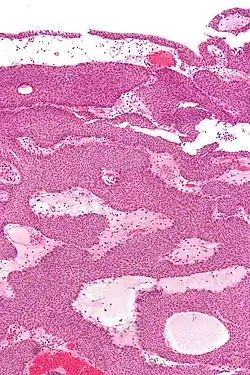

Micrograph of an inverted papilloma of the urinary bladder; H&E stained

An inverted papilloma, also known as Ringertz tumor,[1] is a type of tumor in which surface epithelial cells grow downward into the underlying supportive tissue. It may occur in the nose and/or sinuses or in the urinary tract (bladder, renal pelvis, ureter, urethra). When it occurs in the nose or sinuses, it may cause symptoms similar to those caused by sinusitis, such as nasal congestion. When it occurs in the urinary tract, it may cause blood in the urine.